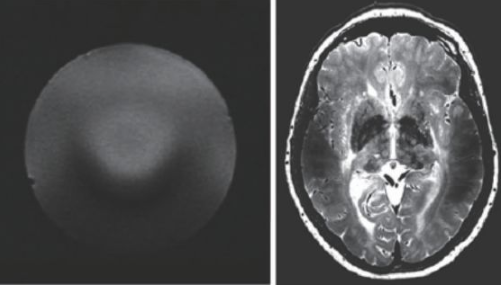

因此,磁共振成像技術目前的發展趨勢,是朝著更高磁場強度發展,以期獲得更高分辨率的圖像,并實現多核成像。圖6 顯示了磁場強度的高低對圖像分辨率的影像,(a)為7 T 磁場下的圖像,(b)為0.35 T磁場下的圖像,二者的圖像分辨率可見一斑。

圖6 T2 加權成像(a)7 T 下的成像,分辨率約0.3 mm;(b)0.35 T下的成像,分辨率約1 mm